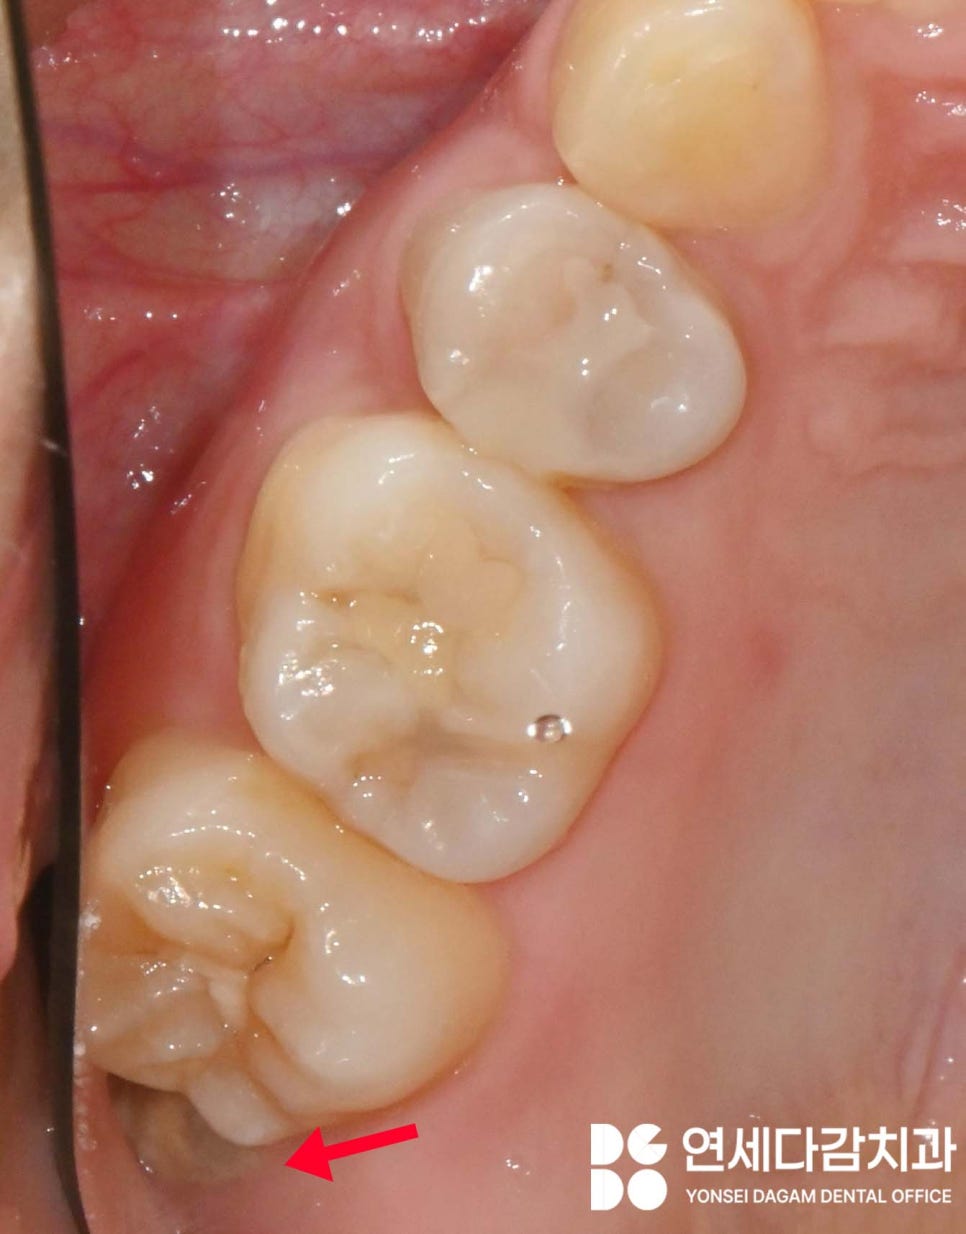

특히 위턱 매복 사랑니 중에서도

인접치 쪽(근심)으로

기울어져 있는 경우에는

개롱역 치과 에서 보여드린 사진처럼

음식물이 자주 끼는 구조가 만들어져

많은 불편감을 느끼게 됩니다.

치관 부분이 앞쪽 어금니를 밀고 있고,

한 번에 제거하기 어려우며,

무리하게 한 번에 빼려고 시도할 경우

인접치 손상이나 과도한 골 삭제가

필요할 수 있습니다.

따라서 이를 조각으로 분리해서

빼는 것이 안전합니다.